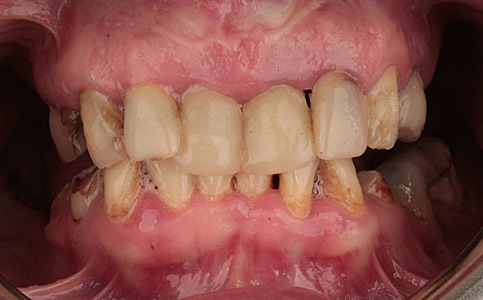

Pacjent zgłosił się do naszego Centrum stomatologii i Ortodoncji FRESHmed w Katowicach w celu poprawnia estetyki swojego uśmiechu. Po konsultacji i dokładnej diagnostyce, usunięto zęby dolne z powodu duzej ruchomości. Zęby zostały zastąpione 6 implantami zębowymi, na których odbudowano cały łuk zębowy dolny metodą All-on-6. Poprawę kształtu i koloru zębów górnych uzyskano poprzez zacementowanie koron pełnoceramicznych.